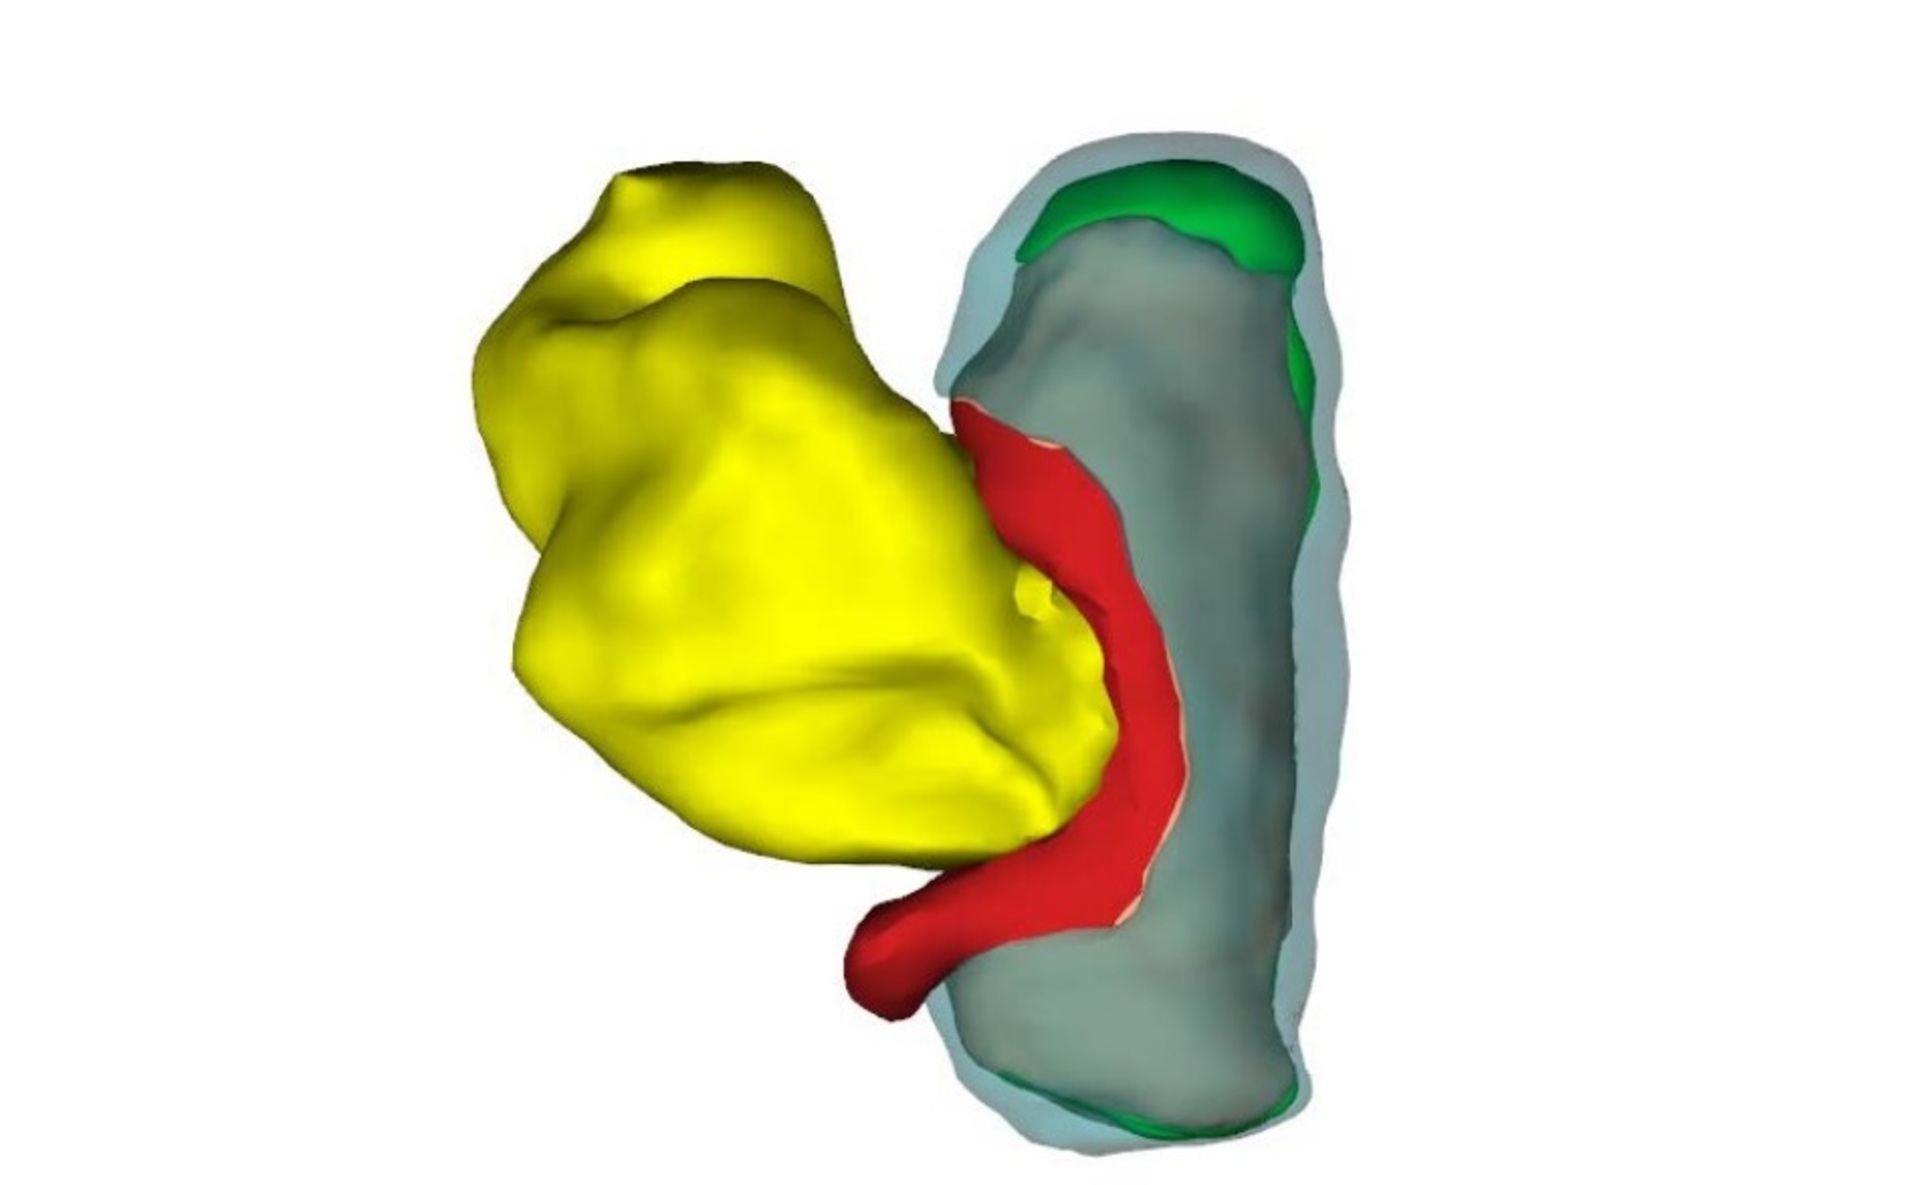

Ученые Академического медицинского центра в Амстердаме идентифицировали и промаркировала 150 структур и органов тела эмбрионов, после чего реконструировали их трехмерные компьютерные модели.

Атлас позволяет рассмотреть как эмбрион в целом, так и его отдельные структуры, органы и системы.